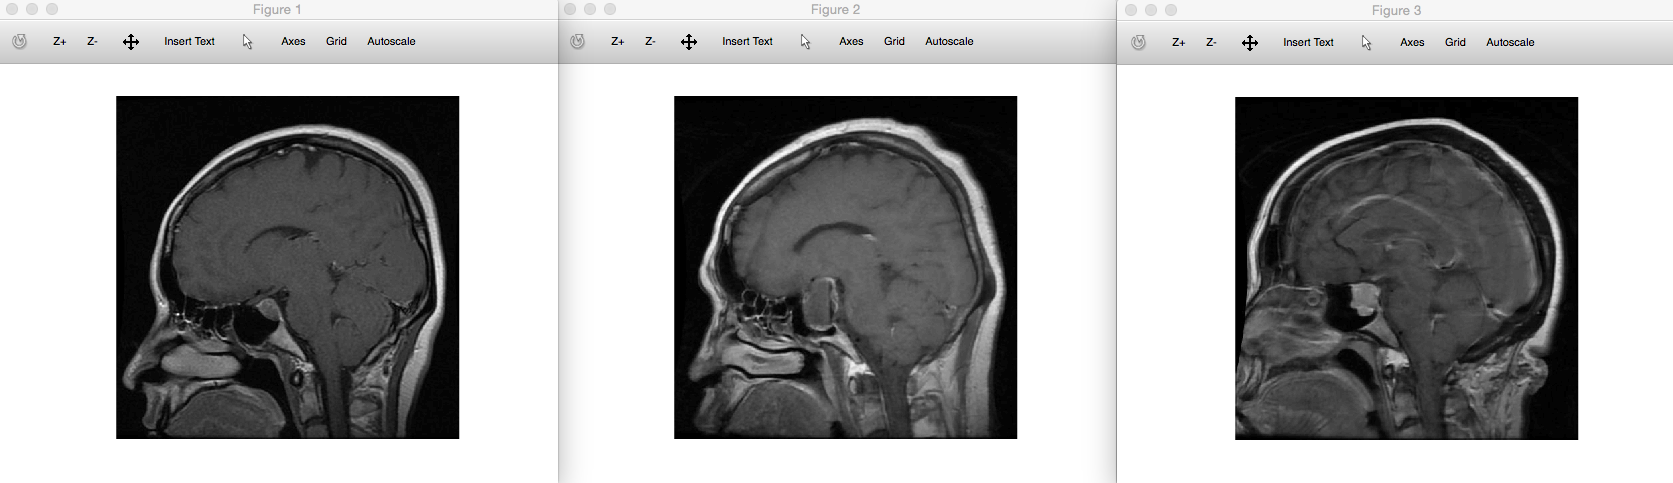

I’ve also applied the supervised clustering algorithm (see the same paper above) to the MRI dataset, which has an accuracy around 94%. This would allow doctors to not only diagnose patients with great accuracy on a cheap computer, since the clustering step would also allow them to compare the most similar brain scans. Clustering the entire testing dataset of 376 rows in this case took about 10 seconds, running on an iMac. For example, the left most image above is an input image of a pituitary brain tumor, and the two images to the right of that are the images returned by the clustering algorithm, both of which also represent brains with pituitary tumors.